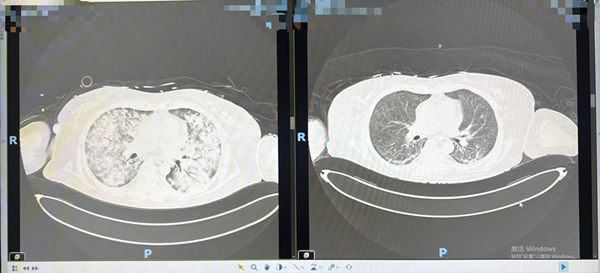

短短几天,病情进展迅速,CT检查显示其肺部已严重受损(俗称“白肺”),肺泡灌洗液快速检测提示耶氏肺孢子菌感染。考虑到李倩病情危重,且有肾病综合征病史,长期口服中药及激素治疗,免疫力低下,被紧急转诊至我院重症医学科抢救。